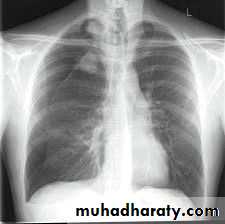

CXR:

closed Pneumothorax